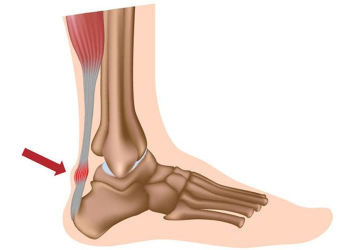

Растяжение ахиллова сухожилия: симптомы и лечение. Отличия от разрыва

Как получается растяжение ахиллова сухожилия. Методы диагностики и отличия от разрыва. Первая помощь, лечение и реабилитация.